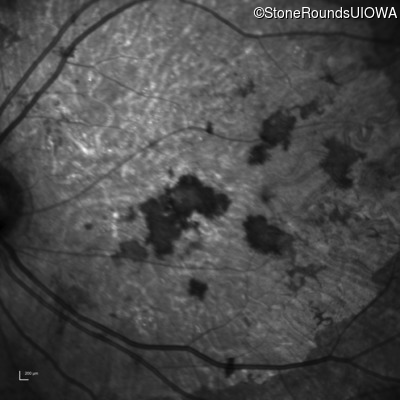

Infrared Fundus Photograph - Right - 20/150 sc

Exemplar